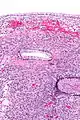

| Micrograph showing a mucinous cystadenoma of the ovary. H&E stain. | |

Mucinous cystadenoma is a benign cystic tumor lined by a mucinous epithelium. It is a type of cystic adenoma (cystadenoma).